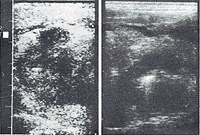

原发性舌癌的二维超声显像特征 本组结果显示原发性舌癌超声显像表现依瘤体大小不同及病变类型不同而异。瘤体小者表现为境界清晰、内部回声尚均匀的低回声结节(图1);瘤体大者(T2期以后)多表现为边缘不光滑、形态欠规则、回声欠均匀的低回声团块。伴瘤体跨越舌中线者,则声像图上舌中隔线连续中断或消失(图2左);溃疡型者,声像图上溃疡面呈高或强回声光点、光斑(图2右);浸润型病灶侵及口底舌外肌者声像图上低回声病灶超出主舌块区(图3),受侵处口底、舌外肌声像失常,舌活动度亦受限。

左 病灶呈不规则不均的低回声结节,舌中线消失

右 旁正中纵切 病灶为低回声区,内见强回声,为溃疡面气体所致

图2 右舌鳞癌

病灶为回声不均匀低回声结节,侵入口底舌外肌,舌中线消失

图3 舌游离部鳞癌 左为正中纵切面,右为横切面